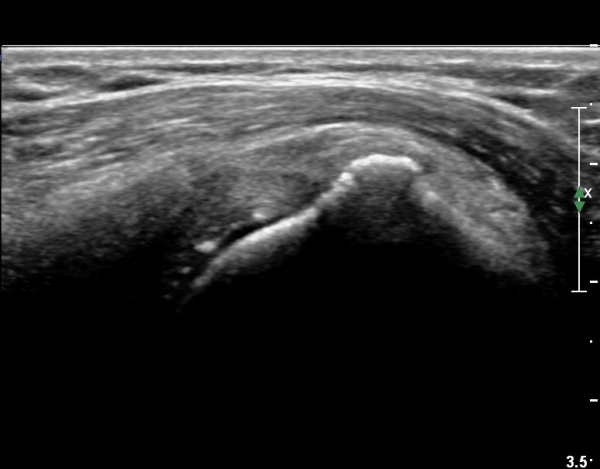

ŽÃËÀÚÀ» °ßºÀ¿ÜÃø¿¡ Á¾À¸·Î ´ë°í ¾î±ú¸¦ ¿ÜÀü ½ÃŰ¸é¼­ °üÂûÇÏ´Ï °ßºÀ¿ÜÃø¿¡ ¼ö¾×Àú·ù°¡ °üÂûµÈ´Ù(»çÁø 5).